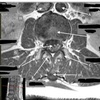

45

What is letter A?

L4-5 INTERVERTEBRAL DISK SPACE

46

What is letter B?

PEDICLE

47

What is letter C?

NERVE ROOTS

48

What is letter D?

CSF

49

What is letter E?

ERECTOR SPINAE MUSCLE

50

What is letter F?

FACET (ZYGAPOPHYSEAL) JOINT

51

What is letter G?

L5 VERTEBRAL BODY

52

What is letter H?

SPINOUS PROCESS

53

What is letter J?

LAMINA

54

What is letter K?

PSOAS MUSCLE